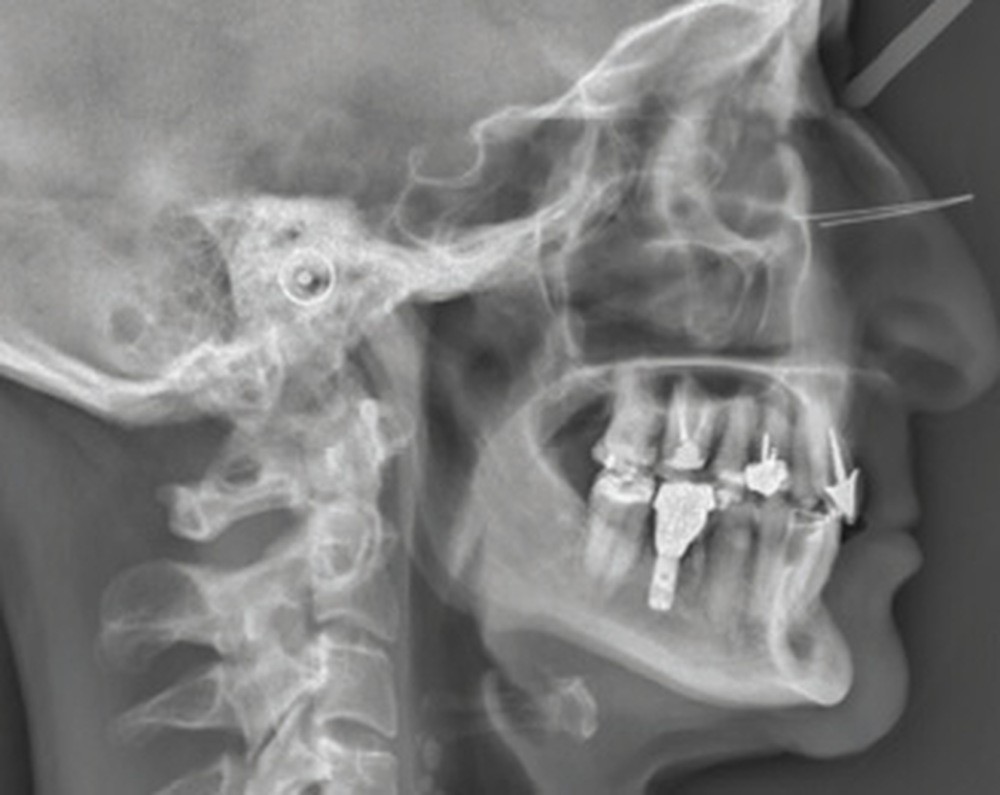

Examens complémentaires (fig. 3)

La téléradiographie de profil et l’analyse céphalométrique montrent une classe I squelettique tendance classe II dans un contexte d’hypodivergence avec diminution de l’étage masticatoire. L’axe de l’incisive mandibulaire est en normoposition, alors que l’incisive maxillaire présente une rétroalvéolie importante.

La supraclusion antérieure est d’origine mandibulaire en lien avec une courbe de Spee marquée quantifiée à 3 mm. L’orthopantomogramme confirme la présence d’un implant en 36.